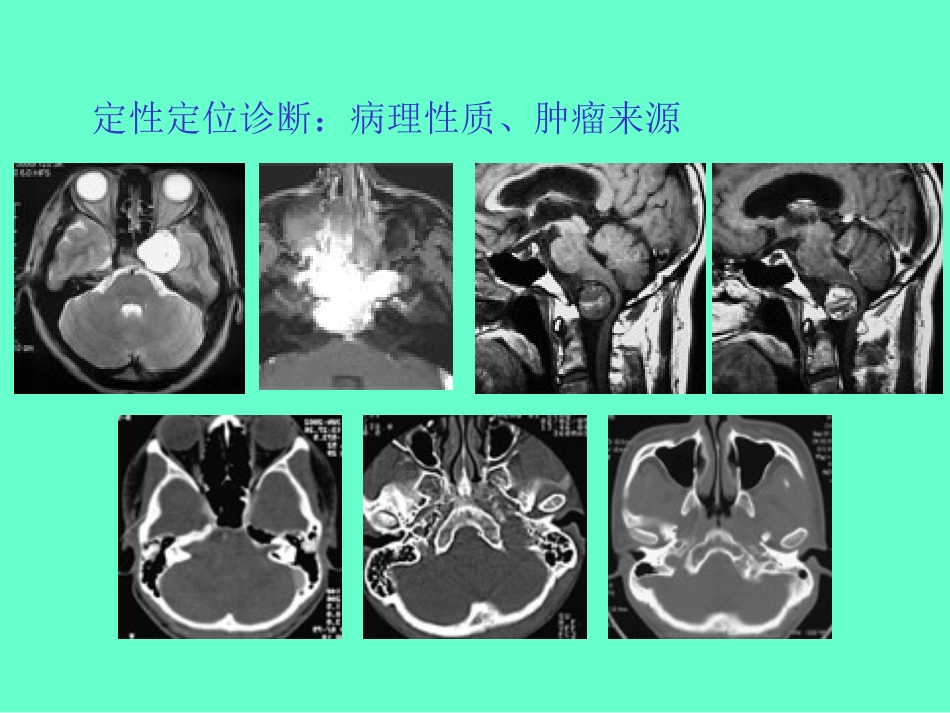

颅底肿瘤的影像学改变与治疗考虑上海华山医院神外徐启武背景:手术越做越大,但疗效并未相应提高微创观念、现代科技发展治疗方案:设计个体化治疗方案手术理念:切除肿瘤与保护神经功能手术入路选择:微创、简单、实用和小型化优化选择围手术期处理和康复治疗放射科与神经外科定性定位诊断:病理性质、肿瘤来源手术入路判断(肿瘤部位与生长方向;Labbé‘s静脉、颈静脉球等;虚拟现实技术手术难度判断(肿瘤质地;肿瘤血供与血管关系;蛛网膜界面肿瘤脑膜瘤颈静脉球瘤软骨肉瘤鼻咽部血管纤维瘤颈静脉孔球瘤枕动脉栓塞前后DSA提高治疗安全度(术前栓塞与放射外科治疗右侧海绵窦海绵状血管瘤射波刀治疗前后MRI眼眶肿瘤发生率0.5~1.5%•海绵状血管瘤•脑膜瘤•视神经胶质瘤•神经源性肿瘤•眼眶转移性肿瘤临床表现•眼球突出•视力减退和眼底变化•眼球运动•眼睑和结膜水肿影像学征象•海绵状血管瘤眶蝶型海绵状血管瘤CT眶内海绵状血管瘤手术前后MRI影像学征象•海绵状血管瘤•脑膜瘤眶蝶型脑膜瘤手术前后CT影像学征象眶蝶型脑膜瘤手术前后MRI影像学征象•脑膜瘤视神经胶质瘤MRI影像学征象•视神经胶质瘤•神经源性肿瘤影像学征象眶鞍型神经源性肿瘤手术前后CT眶鞍型神经源性肿瘤手术前后CT影像学征象•神经源性肿瘤•右眶蝶转移癌右眶蝶转移癌手术前后CT和MRI影像学征象•眼眶肿瘤分型右眶内肿瘤眶外侧壁骨质破坏右眶蝶型肿瘤视神经孔扩大右眶鞍型肿瘤显示眶上裂扩大左眶蝶型肿瘤影像学征象手术治疗海绵窦肿瘤发生率0.1%~0.2%神经鞘瘤脑膜瘤海绵状血管畸形表皮样囊肿临床表现Ⅲ、Ⅳ、Ⅴ、Ⅵ对颅神经眼运动障碍、颜面感觉向前生或向鞍上池内生长视力下降和视野缺损压迫和刺激垂体内分泌失调侵及眶上裂或眶内突眼巨大肿瘤颅内压增高影像学征象•神经源性肿瘤海绵窦神经源性肿瘤手术前后MRI海绵窦脑膜瘤手术前后MRI•脑膜瘤影像学征象影像学征象•海绵状血管瘤海绵窦海绵状血管瘤手术前后MRI影像学征象•表皮样囊肿海绵窦表皮样囊肿(涉及后颅窝)手术前后MRI影像学征象•表皮样囊肿海绵窦表皮样囊肿(涉及后颅窝)手术前后MRI手术治疗经硬脑膜下外侧入路切除海绵窦内神经鞘瘤的术中照片斜坡肿瘤发生率0.3%-1.0%(脑膜瘤•脑膜瘤•脊索瘤•血管纤维瘤临床表现颅神经障碍脑干传导束障碍颅内压增高症状共济失调、痴呆和癫痫等影像学征象•脑膜瘤斜坡脑膜瘤的MRI表现斜坡脊索瘤CT&MRI表现影像学征象•脊索瘤鼻咽部血管纤维瘤MRI影像学征象•鼻咽部血管纤维瘤影像学征象•骨软骨瘤岩斜区软骨瘤MRI手术治疗经后颞下经小脑幕入路切除岩斜型脑膜瘤手术治疗经乙状窦后入路切除岩斜区软骨瘤手术治疗经远外侧经髁入路切除下斜坡脑膜瘤手术治疗经远外侧经髁入路切除(涉及上颈椎的)下斜坡脑膜瘤经额底入路切除蝶斜区硬脑膜外脊索瘤手术治疗手术治疗经乙状窦前入路切除岩斜区脑膜瘤谢谢!